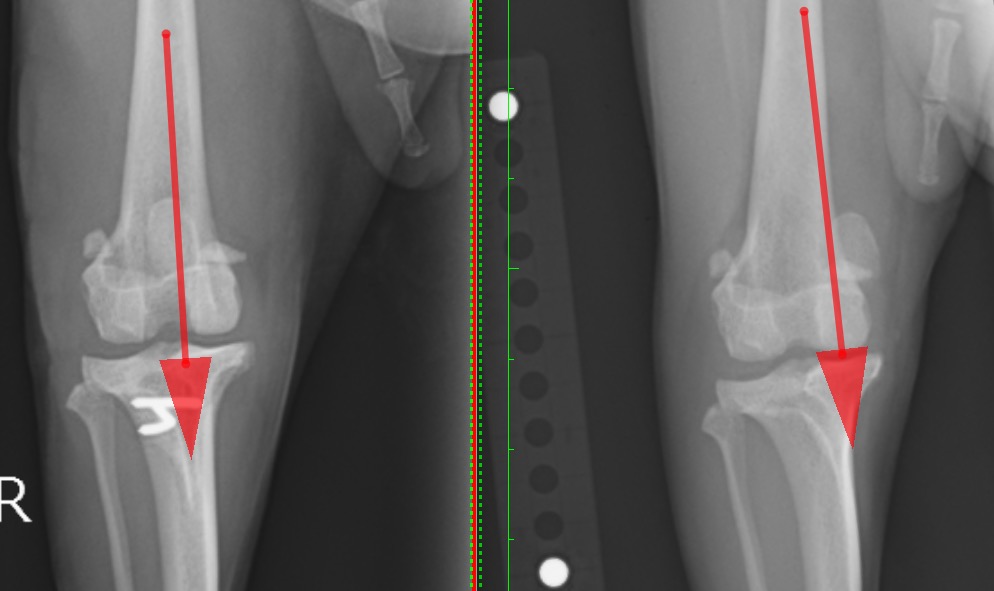

左:脛骨粗面転移術後  右:術前